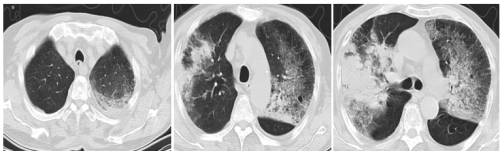

辅助检查:自带当地医院肺ct:双肺多发感染,主动脉钙化,肝左叶类圆形低密度病灶。入院后化验:高敏CRP >200.00 mg/L↑;PCT 12.66ng/ml;血常规:白细胞 4.53 10^9/L、淋巴细胞 0.48 10^9/L↓、淋巴细胞% 10.5 %↓、血小板 125.0 10^9/L、中性粒细胞% 88.1 %↑。心梗2项(肌红、肌钙蛋白):N-末端脑钠肽 4820.00 pg/ml↑、肌钙蛋白I 0.540 ng/ml↑↑。D二聚体 3920.00 ng/ml↑。白蛋白24g/l。肝功、肾功正常。血气分析:(吸氧10l/min):PH:7.42;pCO2:35mmHg;pO2:108mmHg,BE:-1.3,mmol/L, 痰基因8项结果回报:腺病毒,流感病毒、肺炎链球菌。

10.5日我院肺ct:肺ct显双肺片状、大片状高密度影,左侧可见少量胸腔积液。较自带肺ct明显进展。